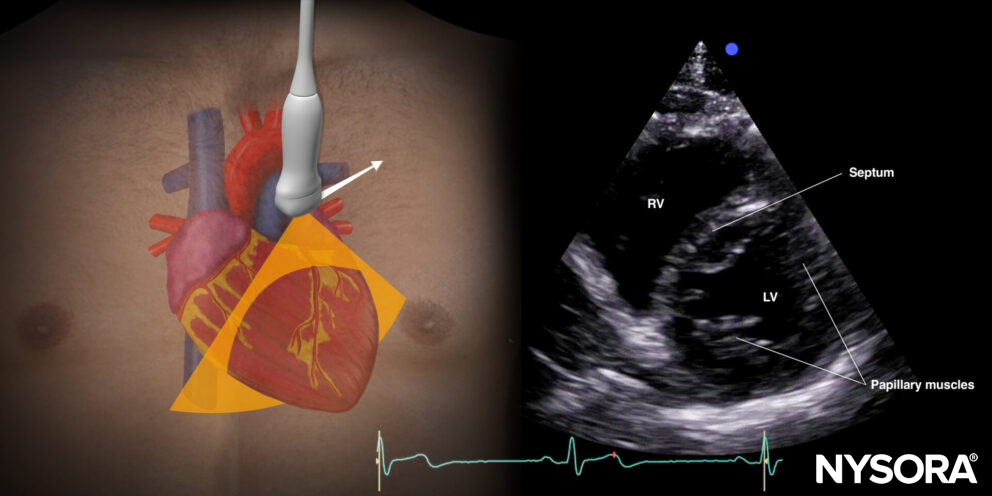

Parasternal short-axis view (PSAX)

Transducer position and sonoanatomy of the parasternal short-axis view.